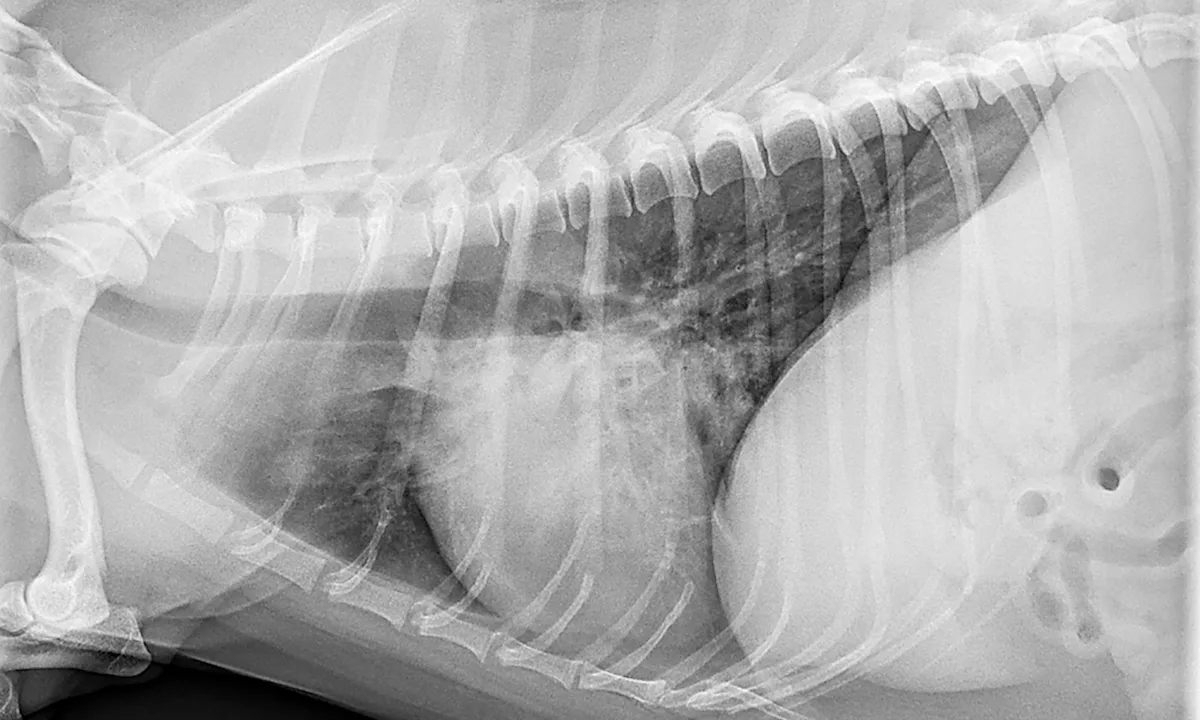

Imaging

Radiographs: Unstructured interstitial, bronchointerstitial, and/or alveolar patterns, depending on pneumonia progression (eg, acute, chronic, resolving)